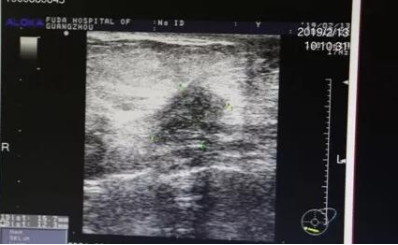

广州复大医院靠谱吗:如何有效治疗焦虑症及幽闭恐惧症的人

这是一位来自英国69岁的女士,八年前她查出乳腺癌,由于她患有严重的焦虑症及幽闭恐...